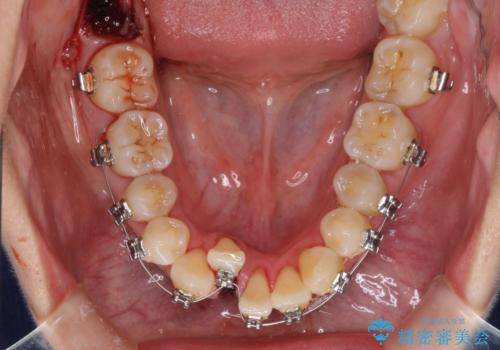

- メタルブラケット

- 治療期間

- 2年8ヶ月

通常であれば、上下顎左右小臼歯各1歯の合計4本を抜歯しますが、歯肉退縮の著しい下顎前歯を抜歯して欲しいという患者様の強い希望により、上顎のみ左右小臼歯2歯を、下顎は前歯を1歯を抜歯することとしました。

抜歯する歯を変更したため奥歯の咬合はアンバランスとなりましたが、前歯は綺麗に整い、歯肉退縮も回避できました。